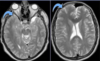

10

30 anos

Esclerose múltipla

Qual o padrão de acometimento das lesões na EM?

Clínica: Idade produtiva 20 - 40 anos; Predomínio em mulheres Lesões focais de hipersinal T2 geralmente maiores que 3 mm e menores que 2 cm no maior eixo, tipicamente ovaladas com distribuição perivenular (perpendicular a superfície ependimária dos ventrículos - padrão em dedos de dawson). Lesões podem apresentar realce sólido ou anelar na fase aguda (realce significa desmielinização ativa). Outras localizações típicas são: corpo caloso e lobo temporal (porém não entram nos critérios diagnósticos).